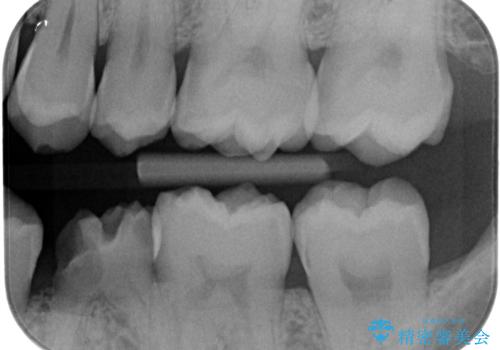

- 検査の結果、奥歯の咬む面に小さな虫歯が確認された患者様です。

虫歯を除去し、セラミックインレーでの修復処置を行います。

表面からは小さな虫歯かのように見えましたが、実際虫歯を取っていくとある程度の大きさがありました。

咬む面の溝は虫歯の好発部位となっています。気を付けて歯磨きができると良いです。